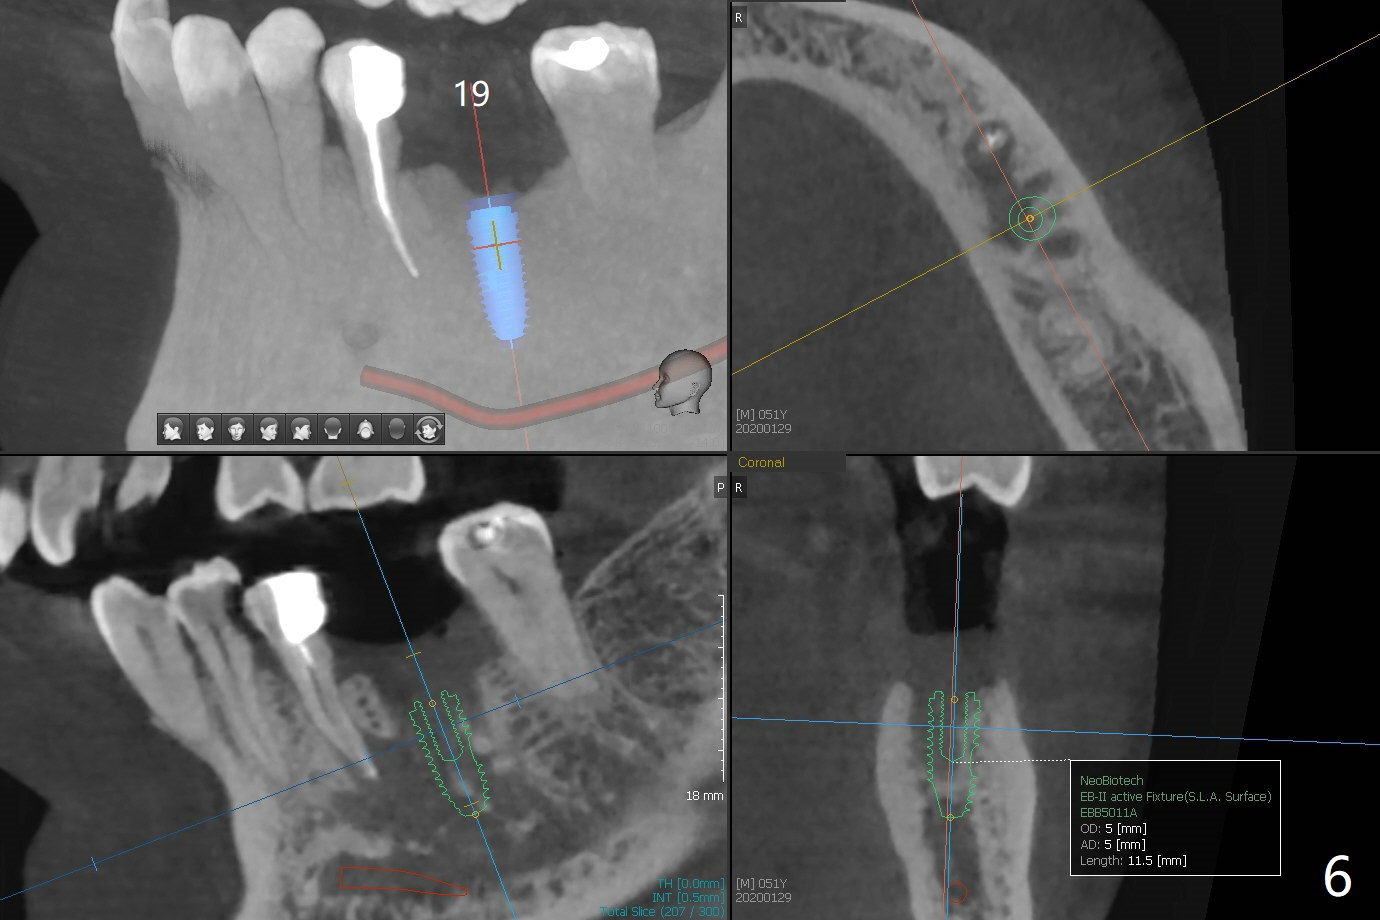

A 51-year-old man with chronic periodontitis requests implants at 19, 24-26 and 30 nearly 2 months post extraction without bone graft (Fig.1). He is willing to quit smoking by using electronic smoke. After SRP, the tooth #6 with supragingival fracture will be saved by post and crown. The mesiodistal space seems to be too narrow for implant (Fig.2). 1-piece implants will be placed at #24 and 26 for FPD (Fig.3,4). Implant placement at #19 and 30 will involve incision, socket redebridement, guide, bone graft (sticky bone), PRF membranes as a barrier and sutures (Fig.5,6).